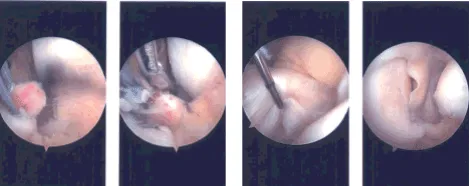

Examination of the medial tibiofemoral compartment showed grade 1-grade 2 osteoarthritic changes of the medial femoral condyle which was cleaned with the use of shaver. It also showed the tear of the medial meniscus root. Rest of the meniscus was healthy. We made a decision to repair the meniscus.

FiberWire sutures were used to pass through the root x 2. Meniscus root repair jig from Arthrex was used to drill a hole through a separate incision. A 70-degree angle was used. The slit was passed down to the bone and a FlipCutter was used to drill a hole of about 5 mm from the posterior margin.

Once the FlipCutter was in, it was flipped and a 5 mm gutter was made for the meniscus to sink in. A passing loop was passed through the tunnel and retrieved. The FiberWire were passed through the passing loop unto the tunnel and brought out near the tibial tuberosity. A good reduction of the meniscus would be seen and pictures were taken and saved.

Intraoperative Arthroscopy Images

The sutures were ported into the tibia with the use of a 4.75 SwiveLock after drilling and tapping. A good reduction and fixation of the meniscus root was achieved. Examination of the intercondylar notch showed an intact ACL. E